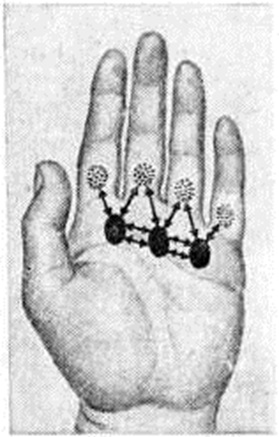

Подкожный Панариций— воспаление подкожной клетчатки пальца (рисунок 1, 4) — наиболее распространённая форма Панариций Чаще встречается подкожный Панариций ладонной поверхности дистальных фаланг. Так как на тыльной поверхности пальцев кожа подвижная, а подкожная клетчатка рыхлая и содержит много лимфатических, сосудов, широко анастомозирующих с лимфатических, сосудами ладонной поверхности, то при расположении гнойного очага на ладонной поверхности пальца отёк, припухлость и гиперемия кожи более чётко выражены на боковых поверхностях и тыле пальца. Палец (или фаланга) увеличивается в объёме, становится напряжённым (цветной рисунок 2, 3). Большая толщина, плотность и неподатливость кожи ладонной поверхности, ячеистое расположение подкожной клетчатки способствуют быстрому распространению воспалительного процесса в сторону надкостницы и сухожилий. Боль постоянная, усиливается при разгибании и ослабевает при умеренном сгибании пальца. Точка наибольшей болезненности соответствует локализации центра гнойного очага. Часто больной лишается сна из-за боли, изнурён, температура тела повышается до 38—39°. В гнойное воспаление могут вовлекаться кость, сухожилия, суставы (рисунок 2). Из очага, локализующегося в проксимальной фаланге пальца, гнойный процесс может перейти по рыхлой клетчатке межпальцевых промежутков в каналы червеобразных мышц, дистальный отдел ладони и на проксимальные фаланги соседних пальцев (рисунок 3).

Сухожильный Панариций— гнойное воспаление влагалища сухожилия и сухожилия пальца (рисунок 1, 7). Воспаления сухожилий разгибателей пальцев, как правило, не бывает. Сухожилия сгибателей пальцев обычно вовлекаются в процесс вторично, воспаление переходит на них с влагалища сухожилий. Сдавление тонких сосудов, подходящих к сухожилию через мезотендиний, быстро накапливающимся во влагалище сухожилия экссудатом и тромбоз их приводят в короткие сроки к некрозу сухожилия. Гной из влагалища может прорваться наружу с образованием свища (рисунок 4). При сухожильном панариции I пальца гной может распространяться по влагалищу сухожилия длинного сгибателя большого пальца кисти в общее синовиальное влагалище сгибателей и к V пальцу. Возникает так называемый перекрёстный панариций. Возможно распространение гнойного процесса и в обратном направлении — от V пальца к I. Иногда процесс может перейти на глубокие слои предплечья — в так называемый пространство Пирогова—Парона. Этого не наблюдается при сухожильном панариции II, III и IV пальцев, влагалища сухожилий которых изолированы от общего синовиального влагалища сгибателей кисти. Основной признак сухожильного Панариций—постоянная боль по ходу сухожилия, усиливающаяся при попытке разгибания пальца. Несвоевременное хирургическое вмешательство влечёт за собой некроз сухожилия на большом протяжении, отторжение которого происходит очень медленно. Нежизнеспособное сухожилие выглядит серым, тусклым. Сгибательная функция пальца выпадает.